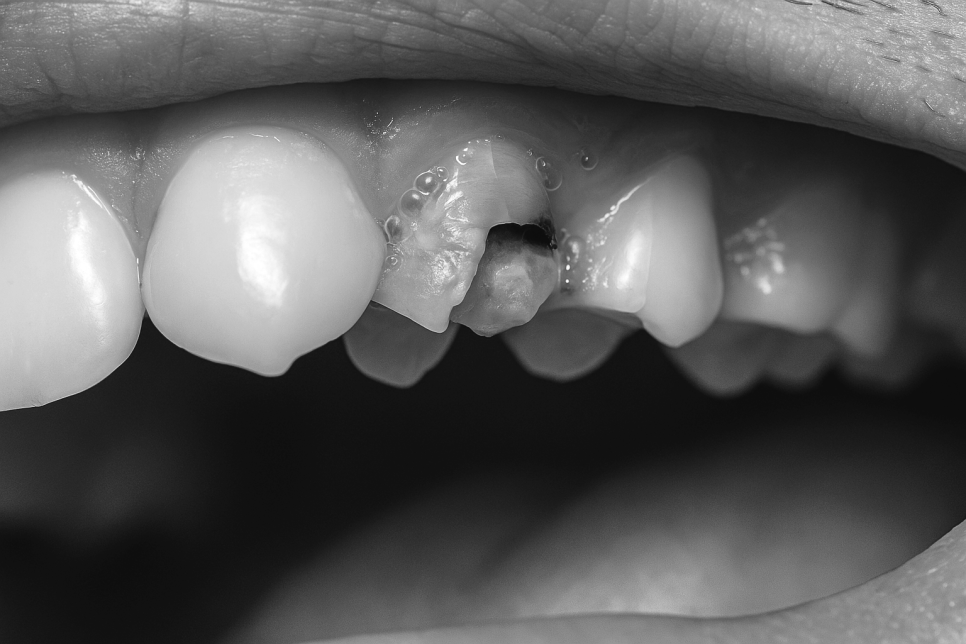

충치가 심한 분일 경우

내부 구조가 약화되었을 수 있습니다.

이렇게 되면 작은 충격을 받아도

이미 내부가 부식되어 쉽게 부러질 수 있고,

특히 신경치료를 받은 곳이라면

영양 공급 자체가 줄어든 후라

더욱 쉽게 깨질 수 있습니다.

본 솔루션은 치아 머리 부분이 잇몸선 아래로

부러지고 소실되어 크라운과 같은 보철치료를

위한 길이 확보가 어려울 때 쓰는 방법입니다.

이때 그냥 기둥을 세우고 크라운으로 덮으면

같은 부위가 다시 부러지게 될 확률이 높아집니다.